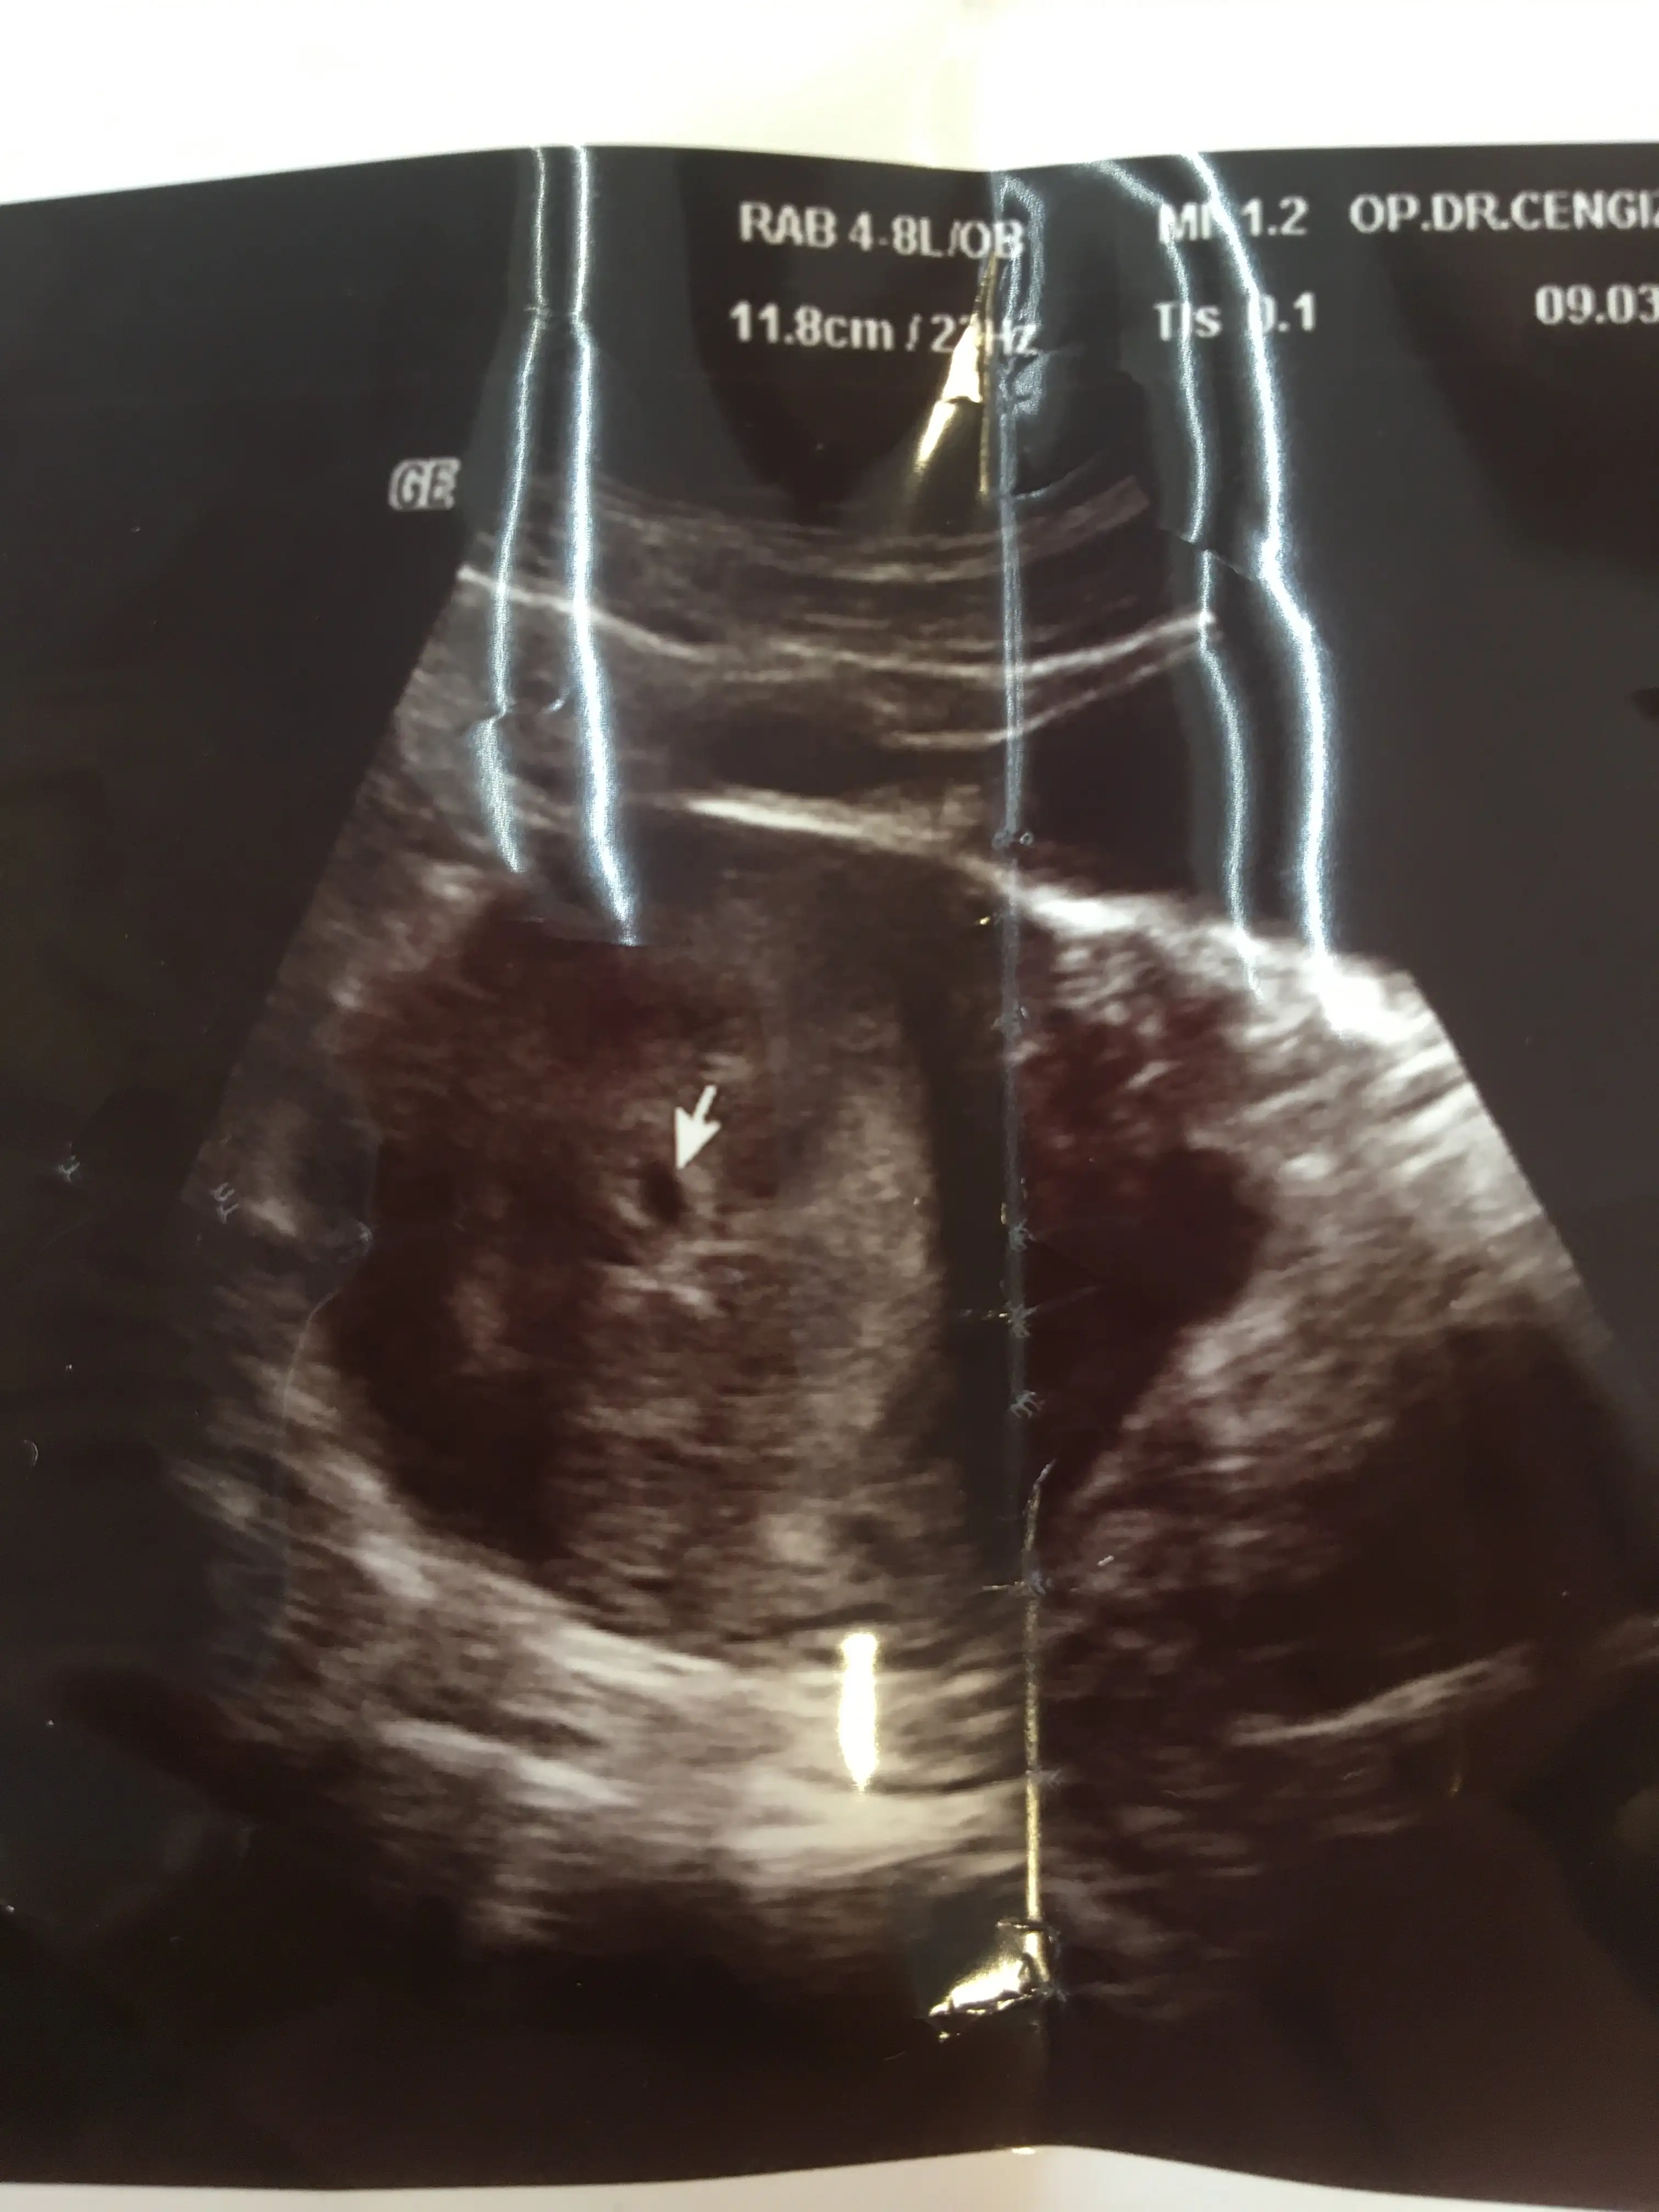

Bugün doktora gittim kese için. 4 mart 554 7 mart 1184 beta hcg doktor yavaş arttığını söyledi. Çarşamba çağırdı kese için tekrar. Bugün acile tekrar kan vericem. Moralim çok bozuldu. Dış gebelik olabilir mi ?